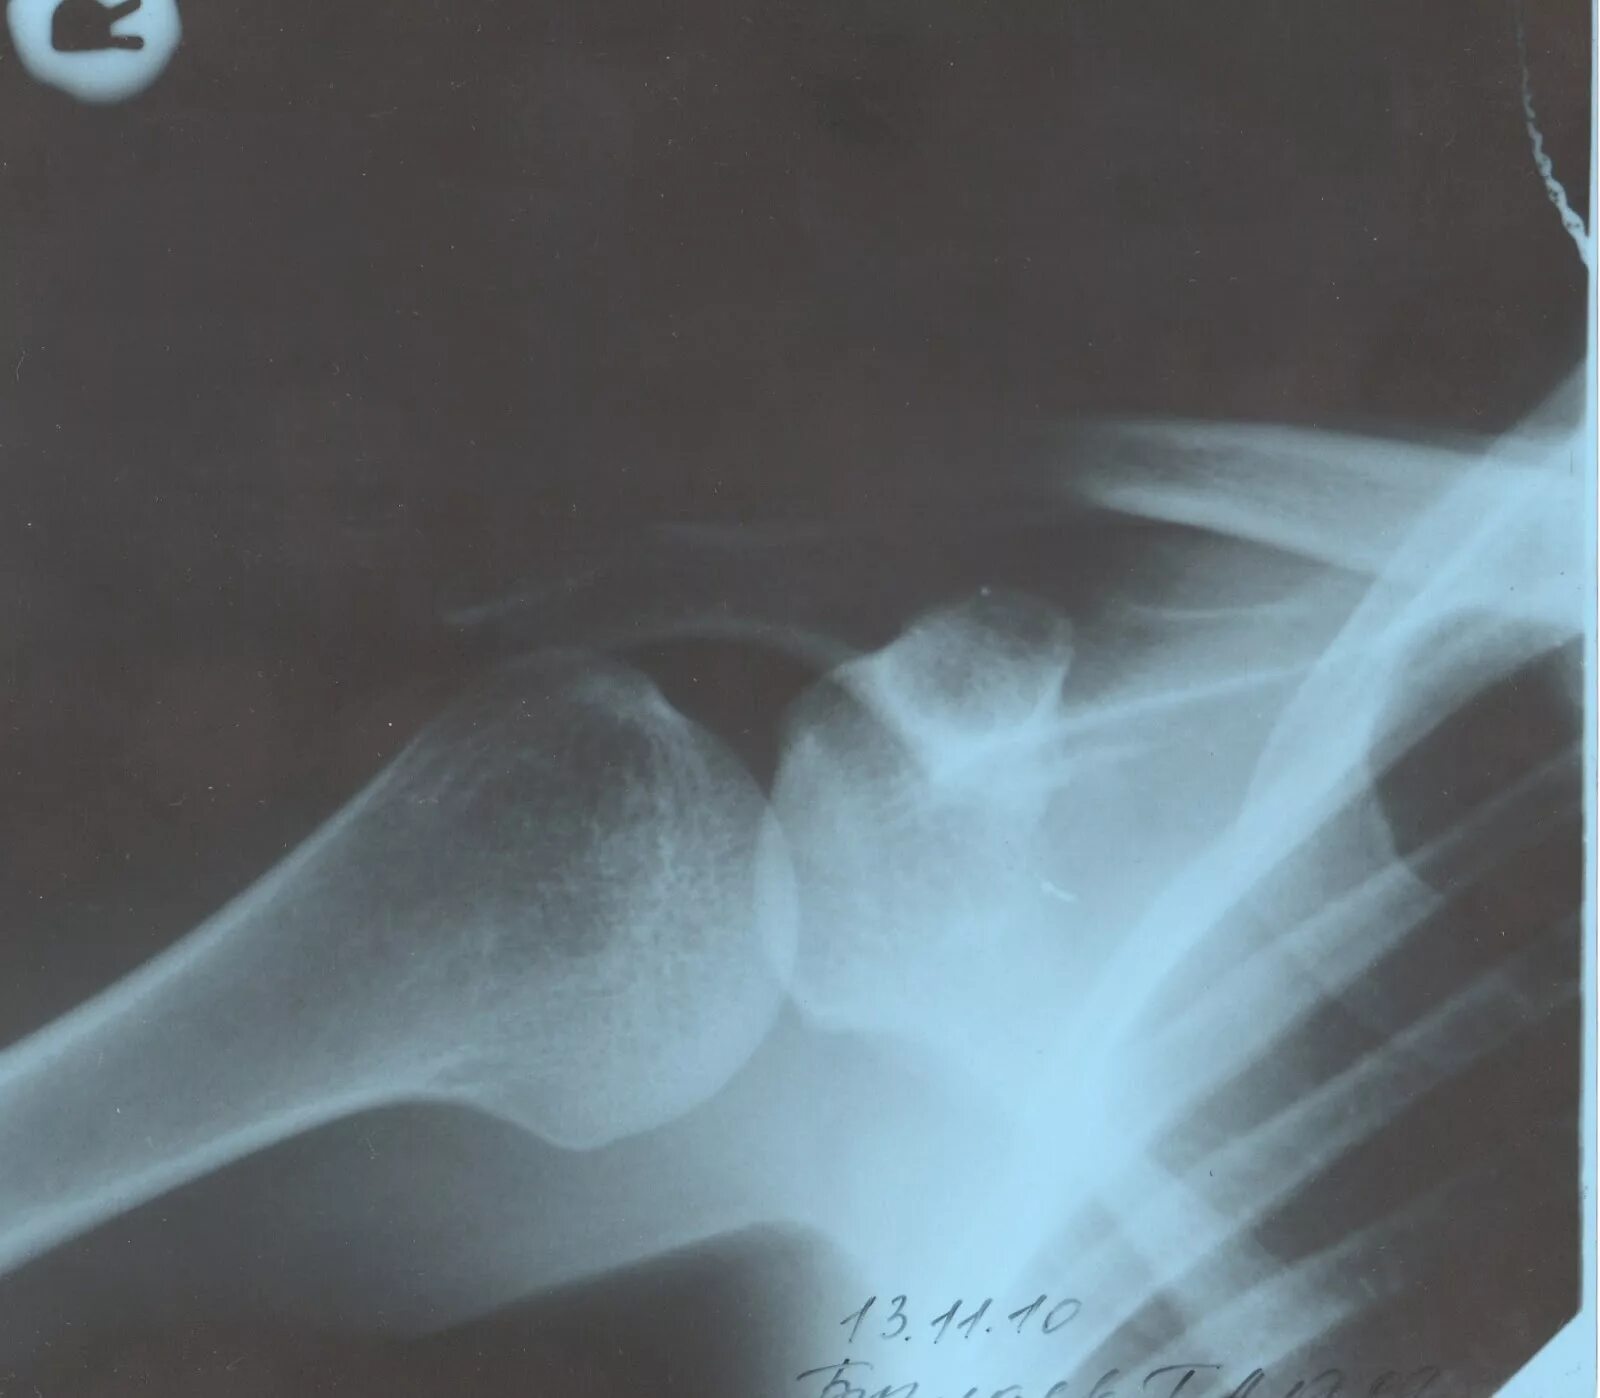

Вывих плеча вверх